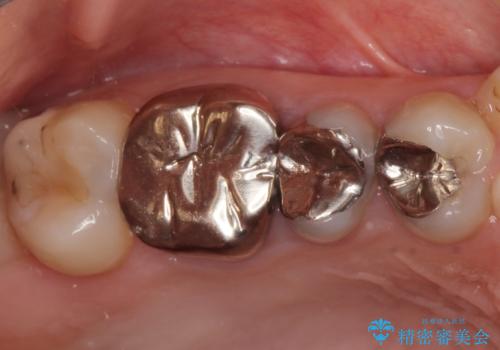

- 笑ったときに見てしまう上顎奥歯の銀歯を気にして来院された患者様です。

折角セラミッククラウンを装着するので、根管治療を行った後に補綴治療を行うこととしました。

他にも目立つ銀歯がありましたが、最も気にしている2本を優先して行うこととしました。